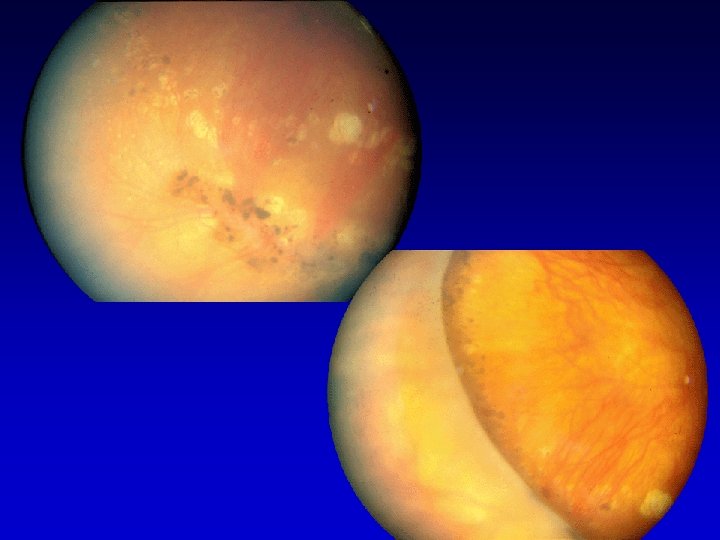

TRATTAMENTO PARACHIRURGICO FOCALE: microaneurismi con diffusione tra 400 -3000 micron dalla fovea; lesioni tra 300 -500 micron dalla fovea se visus <= 5/10 A GRIGLIA: edema maculare PANFOTOCOAGULAZIONE: aree ischemiche > 10Ø papillari CRIOPESSIA TRANSCONGIUNTIVALE DELLA RETINA PERIFERICA: opacità del cristallino, rubeosis iridis, glaucoma neovascolare con residuo visivo

RAZIONALE TRATTAMENTO PARACHIRURGICO DISTRUZIONE AREE ISCHEMICHE ( FATTORI DI CRESCITA) AUMENTO EFFETTO POMPA E. P. ( EDEMA) MIGLIORE DIFFUSIONE OSSIGENO RILASCIO FATTORI ANTIANGIOGENICI REDISTRIBUZIONE EMODINAMICA

EMORRAGIE ENDOVITREALI EMORRAGIE PRE-RETINICHE AL P. P. DISTACCO TRAZIONALE INTERESSANTE LA MACULA IMPALCATURA DEL VITREO ELIMINAZIONE DISTRUZIONE DELLE AREE ISCHEMICHE RETINICHE MEMBRANE NEOVASCOLARI